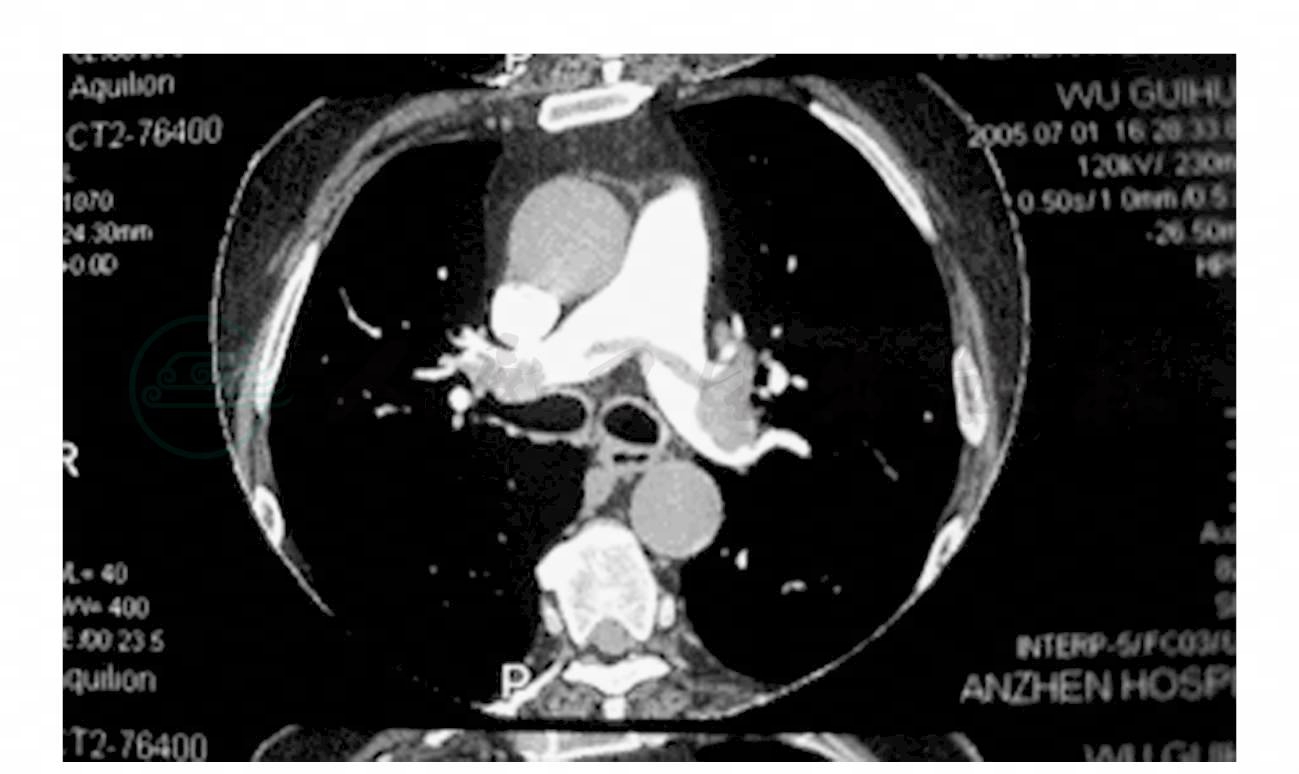

患者湛XX,男性,40岁,于2004年10月1日在外院行股骨干骨折固定术,术后绝对卧床,术后25天查房时活动并按摩患肢后突发胸憋、心悸、出汗,颜面青紫,继而神志不清伴抽搐,以“急性肺栓塞”转入北京安贞医院。入院查体: T 36.8℃,BP 120/75mmHg,R 34次/分,肥胖,面色苍白,口唇微绀,呼吸浅快,心率134次/分,P2>A2,未闻及杂音,腹软,右下肢肿胀。右膝关节(上49mm,下33mm)左膝关节(上51mm,下35mm)。胸部CTPA示:血栓骑跨双侧肺动脉(图1)。UCG示:右心扩大,SPAP 35.5mmHg。

图1 胸部CTPA示血栓骑跨双侧肺动脉